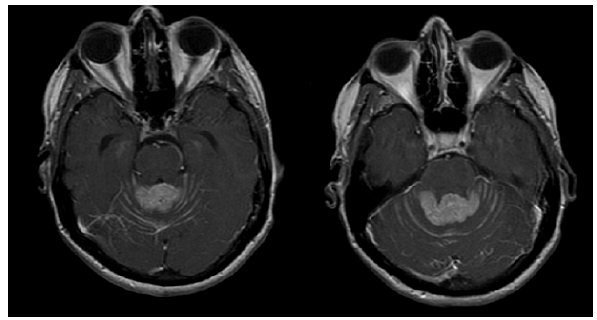

En junio de 2014, la paciente debuta con cefalea, vértigo postural y disminución de la fuerza en el miembro superior derecho, motivo por el cual se solicitó una resonancia nuclear magnética (RNM) cerebral contrastada. A partir de esta se documentó una lesión focal sólida que afectaba el aspecto superior del vermis cerebeloso y el cuarto ventrículo de aspecto metastásico (22 × 17 × 13 mm), asociada a una diseminación leptomeníngea en la fosa posterior. Adicionalmente, se le realizó una RNM de columna cervical, torácica y lumbar con medio de contraste que descartó una afectación metastásica leptomeníngea en esta zona (figura 1)